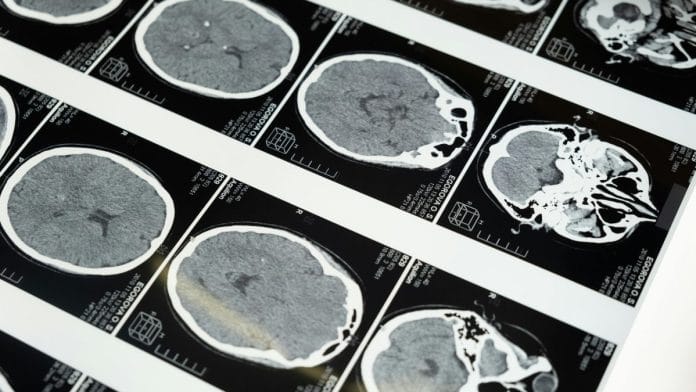

The team initially identified that among all the serotonin receptors in the body, including in various parts of the brain and even the gut, only those in the ventral hippocampal region—the part of the brain that regulates stress- and emotion-motivated behaviors—directly affected anxiety response in the mice, decreasing it in experiments. The neural circuit that was involved in reducing anxiety was also different from the circuit involved in hallucinatory effects, which in mice and rats manifests as a head twitch response.

Subsequently, within the ventral hippocampal region, the team then identified the population of neurons that fired while lowering anxiety.

To understand which region of the brain DOI worked on in the rats, the study team mapped multiple regions of the brain in great detail before delivering the drug to that specific region alone. They identified receptors in the ventral hippocampal region of the brain. When these receptors were blocked and then the drug delivered, there was no anxiety-modulation effect.

In effect, the team found that DOI was causing a specific population of neurons in the ventral hippocampal region of the brain, called PV-positive interneurons, to fire rapidly and light up. This activation of these neurons was identified as the mechanism that tempers anxiety in these rats.